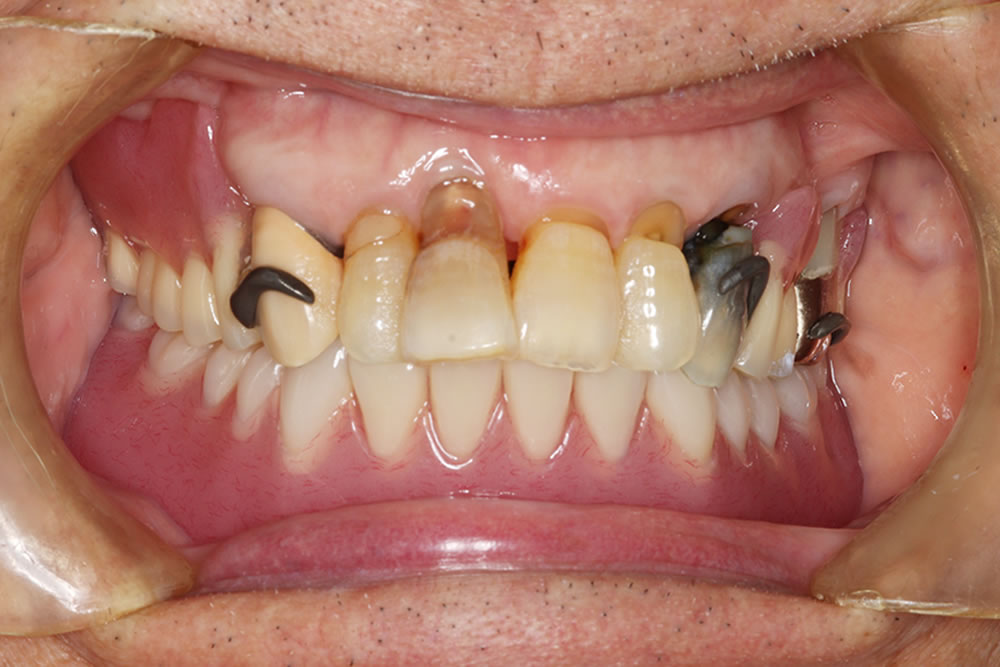

初診時のお口の状態

診察したところ、下顎の顎堤吸収(入れ歯を支える歯槽骨が痩せてしまう状態)が進行し、顎の骨の高さが全体的に低くなっていました。このような顎堤の形態では、通常の総義歯は吸着が得られにくく、義歯の安定が非常に難しい症例となります。